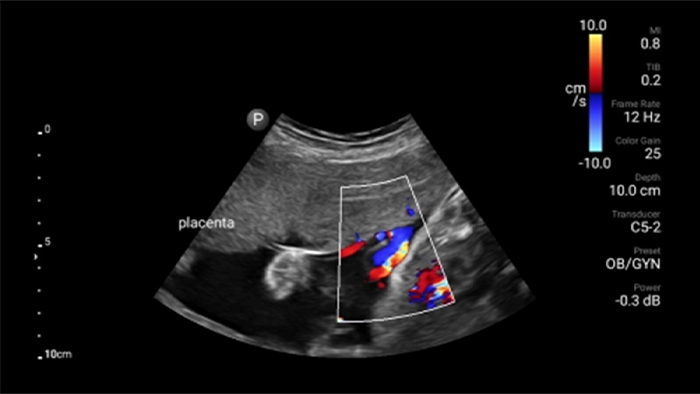

Exceptional ultrasound imaging

Lumify handheld ultrasound offers images that enhance diagnostic confidence.